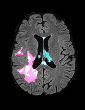

In recent years, data-driven machine learning (ML) methods have revolutionized the computer vision community by providing novel efficient solutions to many unsolved (medical) image analysis problems. However, due to the increasing privacy concerns and data fragmentation on many different sites, existing medical data are not fully utilized, thus limiting the potential of ML. Federated learning (FL) enables multiple parties to collaboratively train a ML model without exchanging local data. However, data heterogeneity (non-IID) among the distributed clients is yet a challenge. To this end, we propose a novel federated method, denoted Federated Disentanglement (FedDis), to disentangle the parameter space into shape and appearance, and only share the shape parameter with the clients. FedDis is based on the assumption that the anatomical structure in brain MRI images is similar across multiple institutions, and sharing the shape knowledge would be beneficial in anomaly detection. In this paper, we leverage healthy brain scans of 623 subjects from multiple sites with real data (OASIS, ADNI) in a privacy-preserving fashion to learn a model of normal anatomy, that allows to segment abnormal structures. We demonstrate a superior performance of FedDis on real pathological databases containing 109 subjects; two publicly available MS Lesions (MSLUB, MSISBI), and an in-house database with MS and Glioblastoma (MSI and GBI). FedDis achieved an average dice performance of 0.38, outperforming the state-of-the-art (SOTA) auto-encoder by 42% and the SOTA federated method by 11%. Further, we illustrate that FedDis learns a shape embedding that is orthogonal to the appearance and consistent under different intensity augmentations.